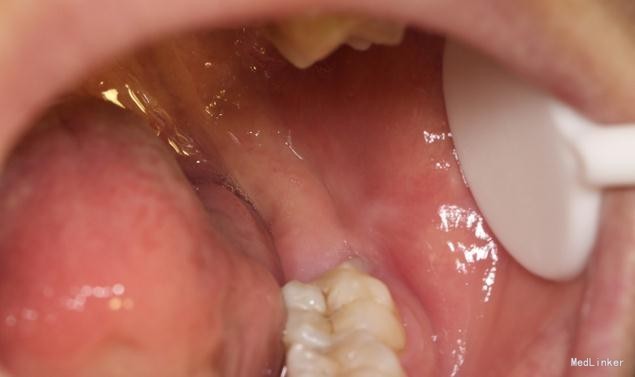

患者,男,25岁,要求拔除左下颌水平阻生牙齿,平素体质一般,无药物、食物过敏史,无高血压、心脏病等系统病史

拔除术

详尽的病例,值得学习。水平阻生的智齿应该尽早拔除,以免后患,极容易在7和8之间形成食物嵌塞而导致7的远中邻面龋坏。8远中的盲袋也易导致冠周炎